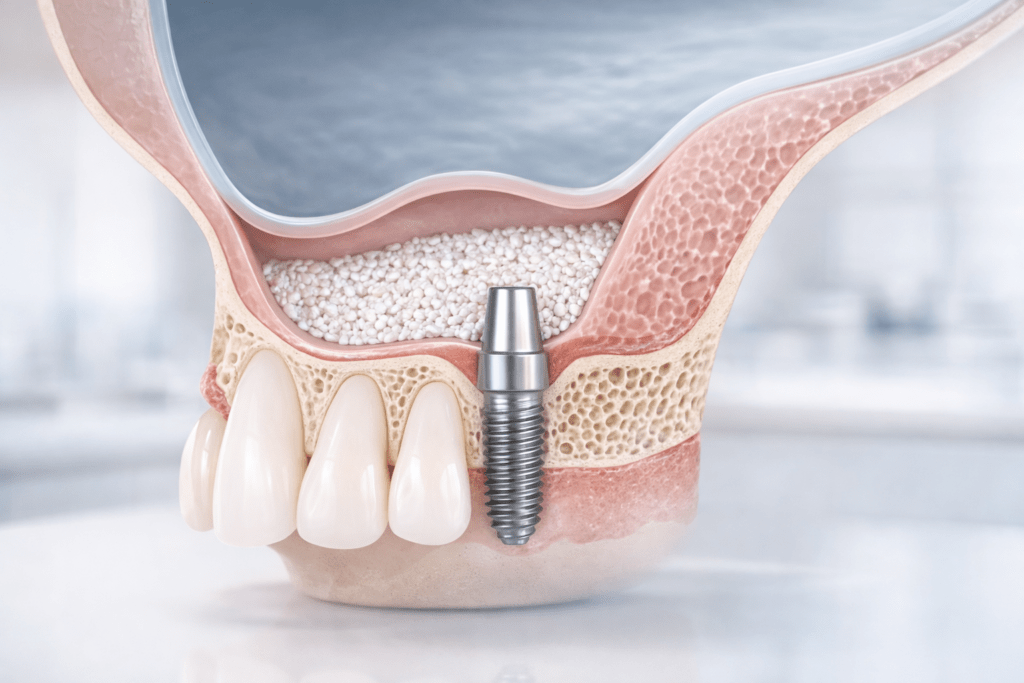

Синус-лифтинг – это хирургическая процедура костной пластики на верхней челюсти, цель которой – увеличить высоту кости под гайморовой пазухой (верхнечелюстным синусом), чтобы затем можно было безопасно и надёжно установить зубной имплант.

Проще: хирург аккуратно приподнимает дно гайморовой пазухи (точнее – её внутреннюю оболочку) и заполняет образовавшееся пространство костным материалом, чтобы кость «доросла» до нужной высоты.

Синус-лифтинг выполняют преимущественно в зоне верхних жевательных зубов (премоляры и моляры), где кость чаще всего становится слишком тонкой после удаления зубов и естественного «рассасывания».

Гайморова пазуха – это воздушная полость внутри верхней челюсти, расположенная над корнями верхних жевательных зубов.

Внутри пазуха выстлана тонкой слизистой оболочкой – мембраной Шнайдера. При синус-лифтинге хирург работает именно с ней: задача – аккуратно отслаивать и приподнимать мембрану, не повредив её.

Высота кости: почему она важна

Чтобы имплант был стабилен, ему нужна достаточная высота и плотность кости. Многие источники для практической ориентации указывают, что для установки импланта высота кости должна быть около 10 мм (иногда допускают 9 мм), а при меньших значениях часто требуется синус-лифтинг.

При недостатке высоты кости имплант либо невозможно поставить безопасно, либо он не получит достаточной первичной стабильности и не сможет нормально прижиться.

В созданное пространство укладывается костный материал (аутокость, алло-, ксено- или синтетический материал – выбор зависит от плана лечения).

Задача материала – создать матрицу для формирования новой кости и обеспечить будущую опору импланту.